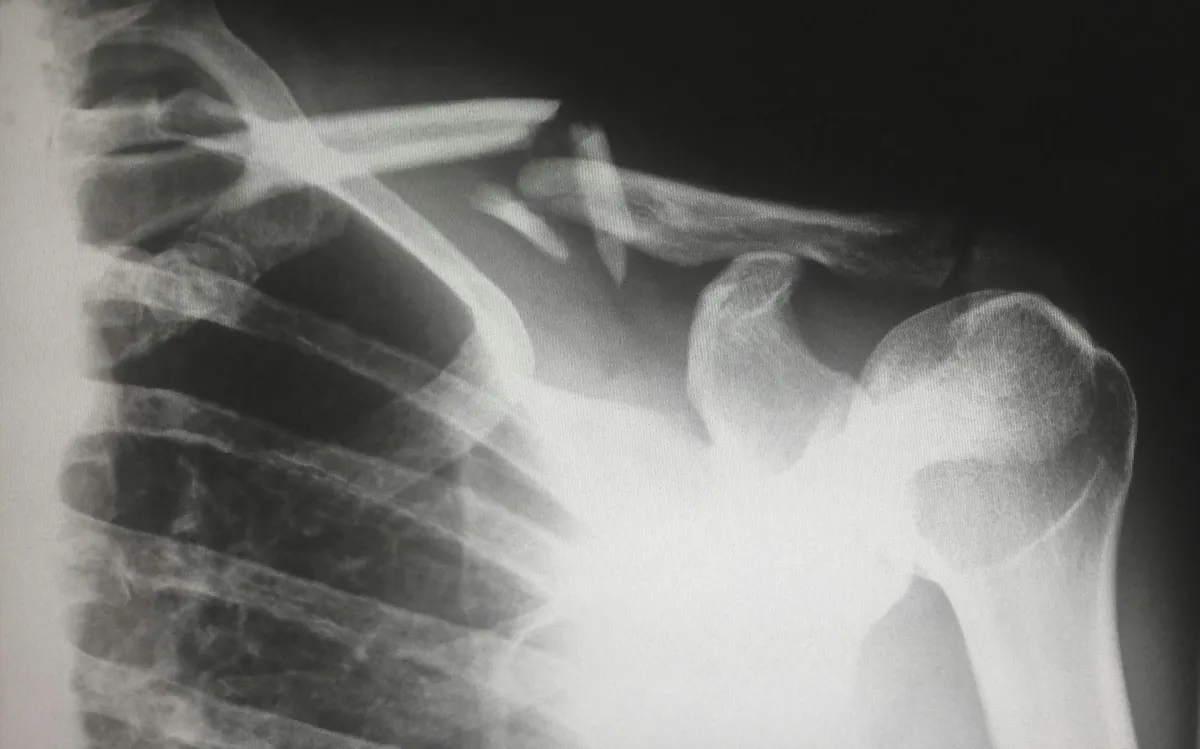

• Medical Records: Obtain all records of your medical treatment, including doctors' reports, X-rays, and any other relevant documents. This is one of the most important pieces of evidence.